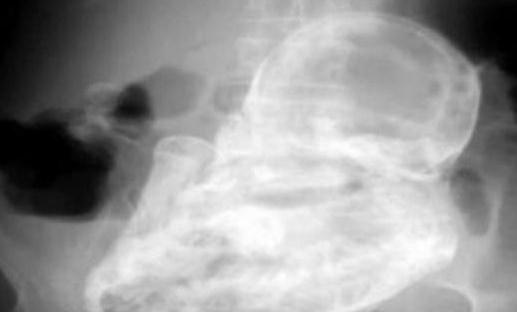

不過(guò),接下來(lái)的發(fā)現(xiàn)卻讓所有人嚇了一大跳——老太太的子宮外竟然有個(gè)未發(fā)育的胎兒,但已經(jīng)死亡了近40年。

這個(gè)“石化胚胎”是怎么形成的呢?醫(yī)生解釋稱(chēng):“由于胚胎未在子宮里發(fā)育,移動(dòng)到老婦的腹腔,導(dǎo)致胚胎無(wú)法正常生長(zhǎng),因而鈣化形成石胎。”